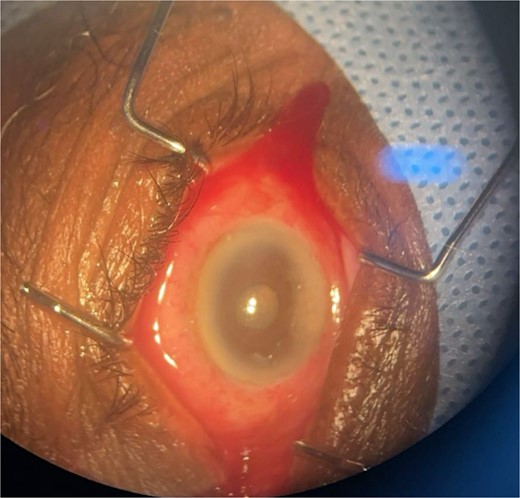

Patient 3: A 63-year-old Saudi female reported pain and decreased vision in her right eye. On examination 4 days post-surgery, her vision was PL. Examination findings included severe conjunctival injection (Fig. 5). B-scan (Fig. 6). Treatment included vitreous tap and intravitreal antibiotics.

Surgical microscope examination showing hypopyon, chemosis, ciliary, and conjunctival injection in patient 3.